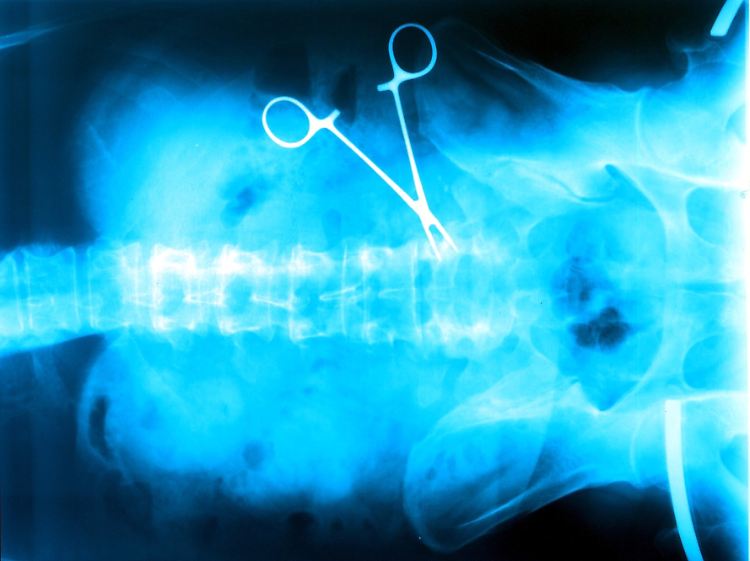

Beschwerden wegen Behandlungsfehlern von Ärzten nehmen deutlich zu.

(Foto: dapd)